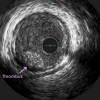

May 20, 2016 — Using optimal frequency domain imaging (OFDI) to guide percutaneous coronary intervention (PCI) with…